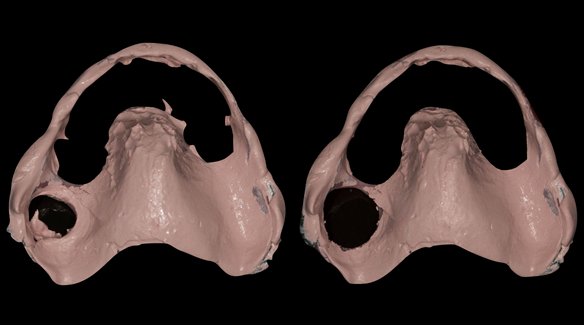

- The remaining natural upper natural teeth and lower back molars were heavily restored having generalised periodontitis stage 4 Grade C. Some of the teeth exhibited caries. The prognosis for these teeth ranged from dubious to hopeless.

The clinical situation and treatment process is shown in detail below with photographs. In addition, threre is a link to the a 45 minute webinar I gave explaing this case. I provided the clinical work and Rowan Garstang provided the technical work.